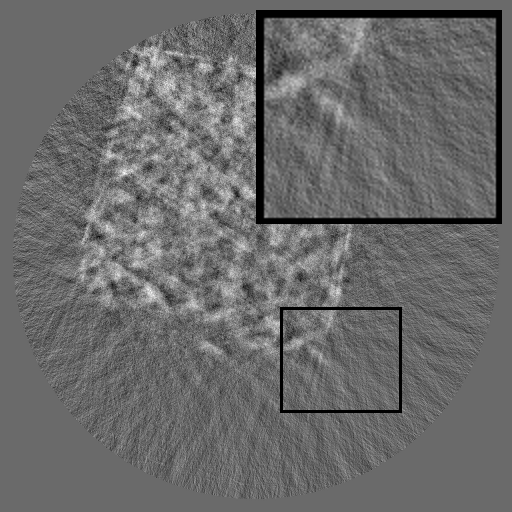

Figure 2: Qualitative inpainting results on TomoBank (lines 1 to 2) and LoDoPaB (lines 3 to 4) with random mask (ratio = 0.8) at 1024×\times1024 resolution. Odd columns and even columns show the sinograms and reconstructed images, respectively.

Inpainting Quality. Tab 2 summarizes accuracy results. At 2048×\times2048 resolution, HiSin achieves the best performance among all baselines while remaining memory-efficient, demonstrating its ability to extend high-quality inpainting to resolutions where other diffusion models fail. At 1024×\times1024, HiSin delivers accuracy comparable to its computation-intensive counterpart RePaint, showing that our optimizations do not compromise fidelity at moderate scales. Compared to DiffIR and HiDiffusion, HiSin consistently achieves higher SSIM and PSNR across mask ratios, with improvements up to +0.03 SSIM and +1.8 dB PSNR. Fig 2 visualizes sinogram inpainting and reconstructed images, where HiSin produces nearly indistinguishable results from RePaint. These findings confirm that HiSin fundamentally extends diffusion-based inpainting to 2048×\times2048 resolution in a more memory- and runtime-efficient manner.